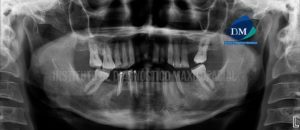

Paciente pediátrico de sexo masculino acude al Instituto de Diagnóstico Maxilofacial para evaluación imagenológica. En la radiografía panorámica observamos las estructuras óseas de características conservadas,